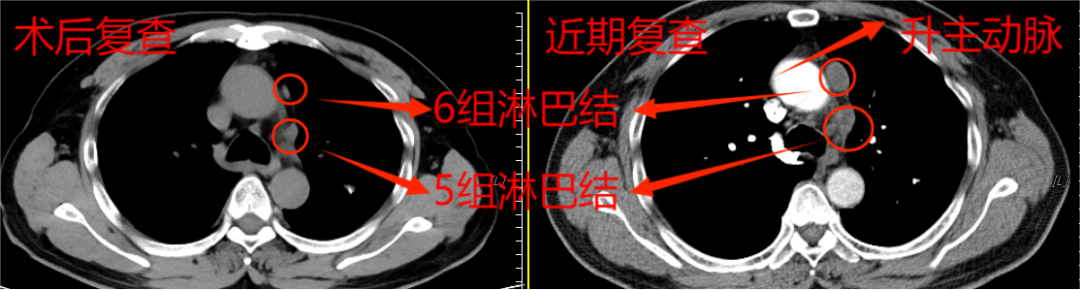

患者吳阿伯,60歲,家住南安市碼頭鎮(zhèn),半年前在他院發(fā)現(xiàn)食管早癌,順利做了胃鏡下早癌剝離術(shù),住院期間檢查發(fā)現(xiàn)左上肺舌段1.3cm的結(jié)節(jié),遂又行雙孔胸腔鏡下左上肺舌段切除術(shù),術(shù)順。術(shù)后定期來我院復查。近期復查ct時發(fā)現(xiàn)縱隔5、6組淋巴結(jié)明顯腫大,全身petct考慮轉(zhuǎn)移。

這下讓外科手術(shù)團隊為難了,因為兩組淋巴結(jié)臨近主動脈及左肺動脈2處大血管,位置深,即使CT引導下穿刺活檢,僅毫厘之差,仍大概率會出現(xiàn)大出血、氣胸,甚至危及生命,需緊急開胸,不活檢。由于轉(zhuǎn)移瘤性質(zhì)難定,影響后續(xù)方案的制定,家屬也很焦慮。